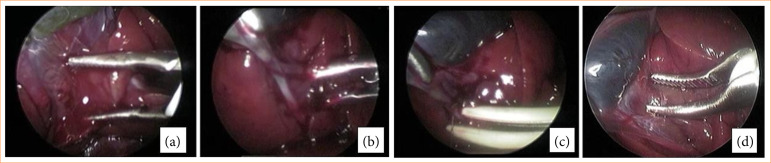

Purpose: Laparoscopic cholecystectomy (LC) is the gold standard for the treatment of gallbladder (GB) disease in small animals. The aims of this study were to investigate and compare the effect of different types of dissectors during LC in rabbits; electrothermal bipolar vessel sealing device (EBVS-LigaSure) and standard electrosurgical dissection (bipolar Maryland) for dissection of the GB in LC, correlating liver function tests (LFTs) in pre and postoperative periods (days 0, 3, 7, 15); macroscopic checking 15 days after surgery through necropsy; histopathological, bacteriological through bacterial growth by culture and intraoperative complications.

Methods: Twenty rabbits were used, group (n = 10) using EBVS for GB dissection and cystic duct seal (GLL), and group (n = 10) using bipolar dissecting forceps and EVBS for cystic duct seal (GLE).